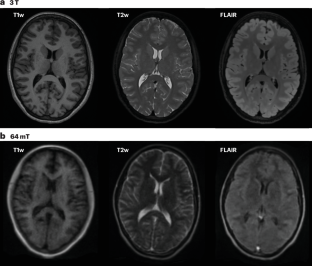

Váša, F. et al. Ultra-low-field brain MRI morphometry: test–retest reliability and correspondence to high-field MRI. Imaging Neurosci. 3, IMAG.a.930 (2025).

Lee, H. et al. Evaluating brain volume segmentation accuracy and reliability of FreeSurfer and Neurophet AQUA at variations in MRI magnetic field strengths. Sci. Rep. 14, 24513 (2024).

Buchanan, C. R. et al. Comparison of structural MRI brain measures between 1.5 and 3 T: data from the Lothian Birth Cohort 1936. Hum. Brain Mapp. 42, 3905–3921 (2021).

Di Perri, C. et al. White matter hyperintensities on 1.5 and 3 Tesla brain MRI in healthy individuals. J. Biomed. Graph. Comput. 3, 53 (2013).

Hsu, P., Marchetto, E., Sodickson, D. K., Johnson, P. M. & Veraart, J. Morphological brain analysis using ultra low-field MRI. Hum. Brain Mapp. 46, e70232 (2025).